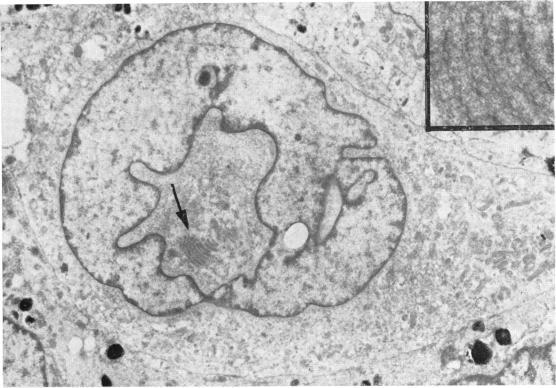

Intranuclear cytoplasmic inclusions have been described previously in both human and animal tissue. So far as we are aware they are described in detail for the first time in this paper in 60 cases of malignant melanoma of the iris, usually in spindle cells. The light microscopic appearances are described, and electron microscopic studies of selected cases show clearly the genesis of these inclusions by cytoplasmic invagination of the nuclear membrane. Their significance is discussed. It is of interest that we have seen identical inclusions in malignant melanomas of the ciliary body, choroid, and conjunctiva but have not as yet reported our findings.